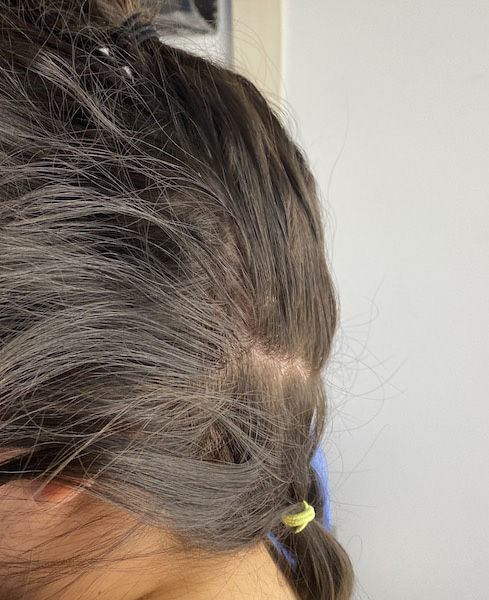

Desire for reduction of sagittal crest that became apparent over the with thinning of the hair.

Mid-sagittal crest skull prominence reduced through a limited scalp incision using high speed burring and large toothed rasps.

Desire for reduction of sagittal crest that became apparent over the with thinning of the hair.

Mid-sagittal crest skull prominence reduced through a limited scalp incision using high speed burring and large toothed rasps.